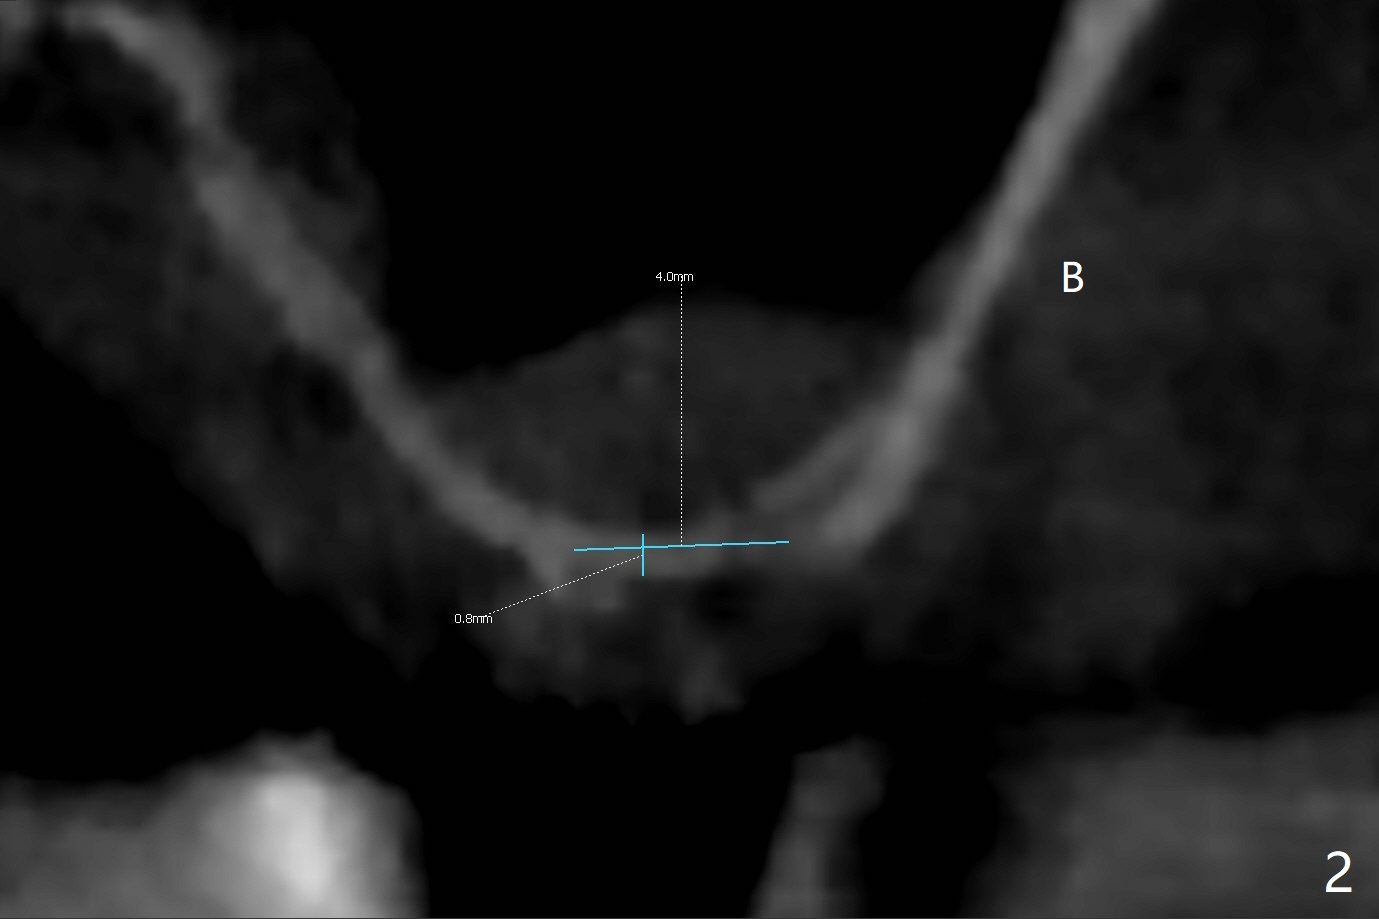

A 68-year-old timid woman is considering implant at #14 twenty months post cementation of #13 and 14 crown (Fig.1). Because of the narrow buccopalatal width (Fig.2 CT coronal section, B: buccal), a 4 mm implant (blue line) seems to be appropriate for the site (Fig.1). After crestal incision and flap reflection, a diamond round bur is used to thin the sinus floor until the bluish membrane is barely visible. An osteotome (Magic Sinus Lifter) is used for penetration. Water lift will be conducted if necessary, considering the already thickened sinus membrane (Fig.3 (CT sagittal section) M). Insert the first PRF membrane, followed by bone graft (not too sticky) repeatedly. Use sensor 1 to confirm lift degree. Try a 4x7 mm dummy FC to test stability. Place a definitive one (probably Magicore) if indicated. Use a second PRF membrane before closure of the wound. After nearly 15 month consideration (including coronovirus), the patient decides to get it done. With incision (Fig.4) and Marking Drill (Fig.5, the sinus membrane barely visible in the middle of the osteotomy (dimple, Fig.6 (black triangle)), the sinus floor does not break upon Magic Sinus Lifter). Later the patient complains of discomfort with tapping. In fact Magic Drill (similar to trephine bur, Fig.7) is used to break into the sinus without membrane perforation (Fig.8). Remember the thick membrane (Fig.2,3). In fact the fractured fragment is attached to the membrane (Fig.9 red lines, green sticky fracture). A small curette is used to further separate the membrane from the bony wall (Fig.10) before insertion of a small piece of PRF and sticky bone. When a 4.5x7 mm dummy implant is incompletely placed with stability (<10 Ncm), the membrane is stretched over the bone graft (Fig.11 M). After removal of the dummy, the major remaining piece of PRF (from 9 cc vial) and more allograft are placed before inserting a definitive implant (same size) with 15 Ncm; still the used to be thick membrane remains intact and stretched (Fig.12 M). The implant is equicrestal buccal, while slightly supracrestal palatal. To prevent implant dislodgement into the sinus and bone graft, a final abutment is placed (Fig.12). The wound is closed with 4-0 PGA, perio glue and perio dressing. The latter dislodges 3 days postop. The wound seems to be healing. No dressing is reapplied.